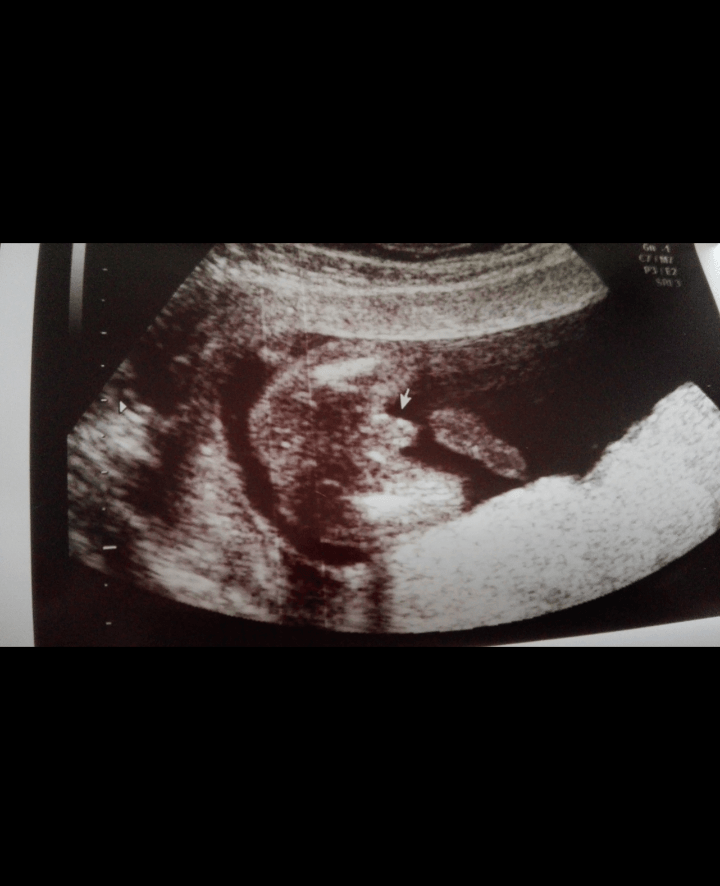

Już po wizycie. 14,5 cm meeeega ruchliwego facecika :) Zdjęcie nie daje złudzeń co do płci maluszka :) Ciężko było ale na koniec pokazał się z przykucu w całej okazałości. Jak powiedziałam synkowi, że będzie braciszek to zobaczyłam najcudniejszy z Jego uśmiechów :) Cieszymy się bardzo :) Lekarz powiedział, że będę za jakiś czas dostawala sterydy bo dzidzia będzie musiała urodzić się max w 38 tyg ze względu na moja historię ciążowa. Narazie o tym nie myślę, jeszcze będzie czas na zmartwienia. Dziś świętujemy małego Franka, Olusia albo jeszcze nie wiem jak bedzie miał na imię ten nasz kolejny Skarb

Załączniki

• IMG_20170628_183113.png

IMG_20170628_183113.png

171,7 KB · Wyświetleń: 128